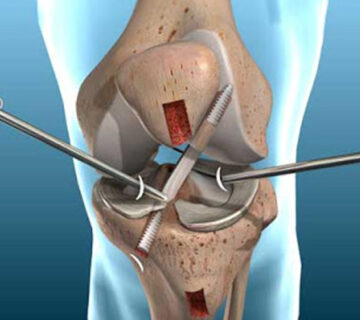

رباط صلیبی

در این مقاله بع فیزیوتراپی دراصفهان | رباط صلیبی | بهترین فیزیوتراپی دراصفهان | دکتر قولنج | drgholenj | درمان درد ... اطلاعات بیشتر